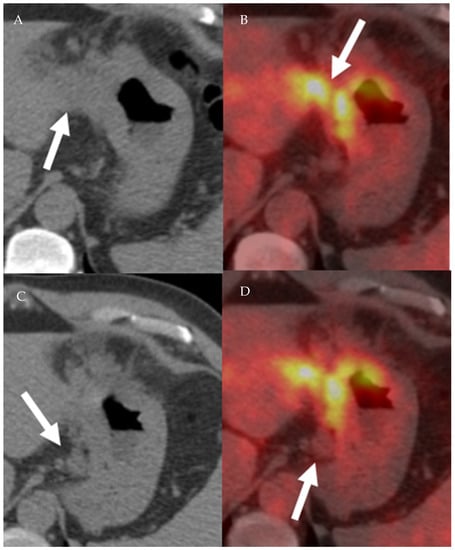

4.1.3. Positron Emission Tomography (PET) and Positron Emission Tomography-Computed Tomography (PET-CT)